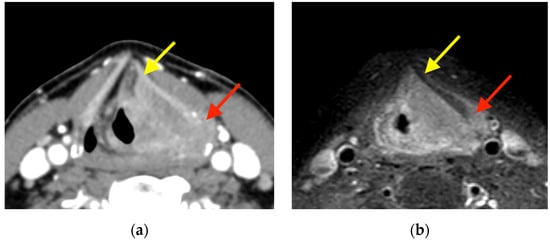

2.5.1. CEUS Imaging

2.5.2. Cross-Sectional Imaging